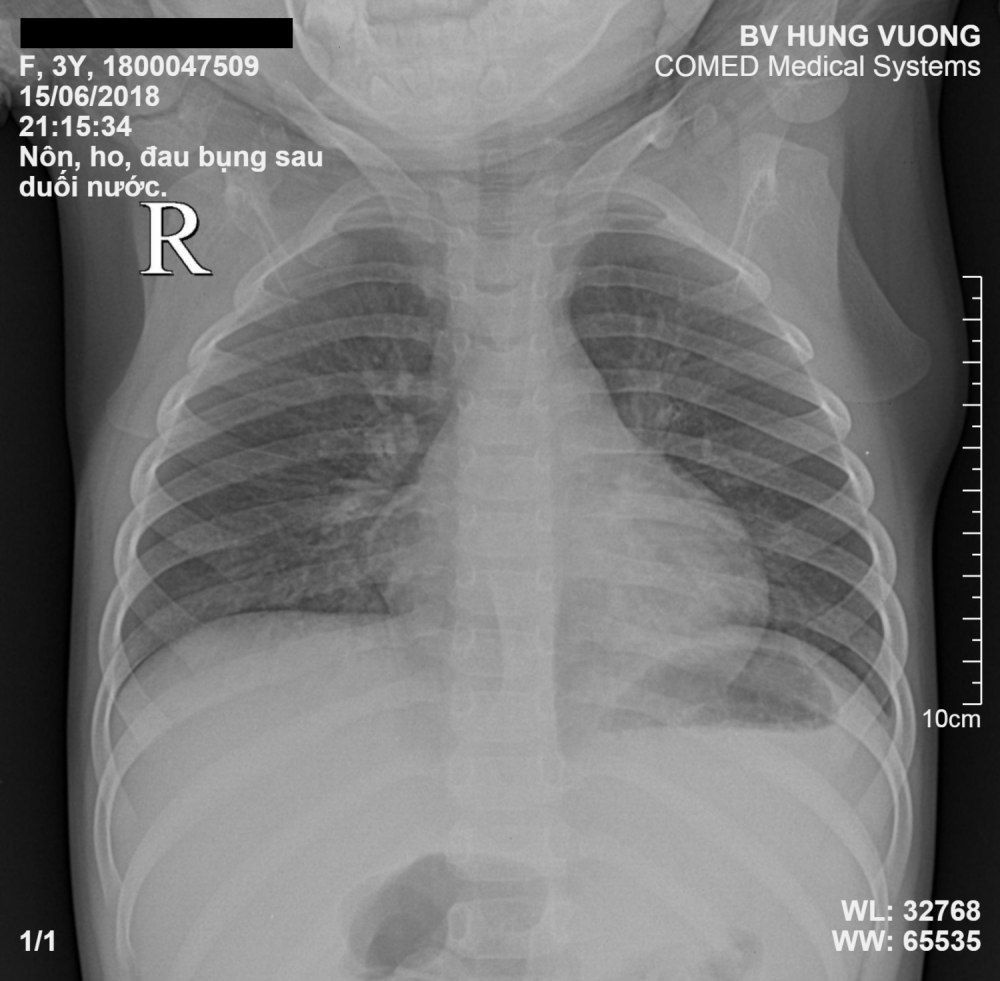

Bệnh nhi được thăm khám và chụp XQ phổi, kết quả XQ cho thấy hình ảnh phổi bé bị viêm. Các bác sĩ chẩn đoán bệnh nhi bị viêm phổi do đuối nước.

Hình ảnh X-quang phổi của bệnh nhi.